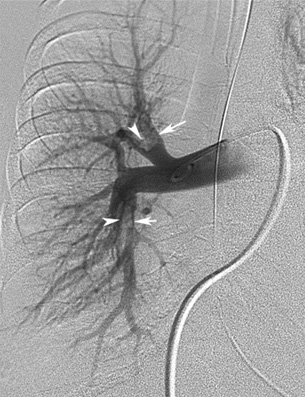

Pulmonary Angiogram: Pulmonary Emboli

Intraluminal defects in the right upper lobe and lower lobe branches of pulmonary artery.